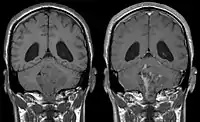

Ependymoma of 4.ventricle in MRI. Left without, right with contrast-enhancement.